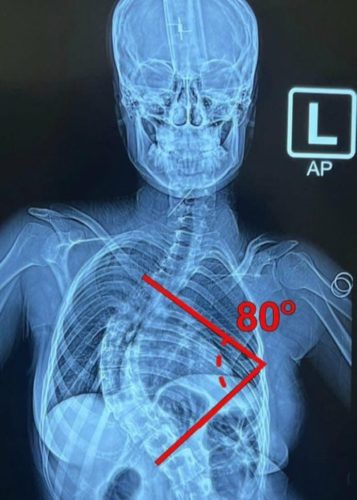

وأكد الدكتور فراس العبيدي، أحد رواد جراحة العمود الفقري في العراق، بمساهمته بشكل فاعل ليس فقط في إعداد وتدريب الكوادر، بل أيضًا في إجراء العشرات من عمليات تصحيح اعوجاج العمود الفقري في مدينة الطب بأيادٍ عراقية خالصة، والتي أصبحت اليوم تُجرى كإجراءات روتينية بفضل تراكم الخبرة والدعم المؤسسي.